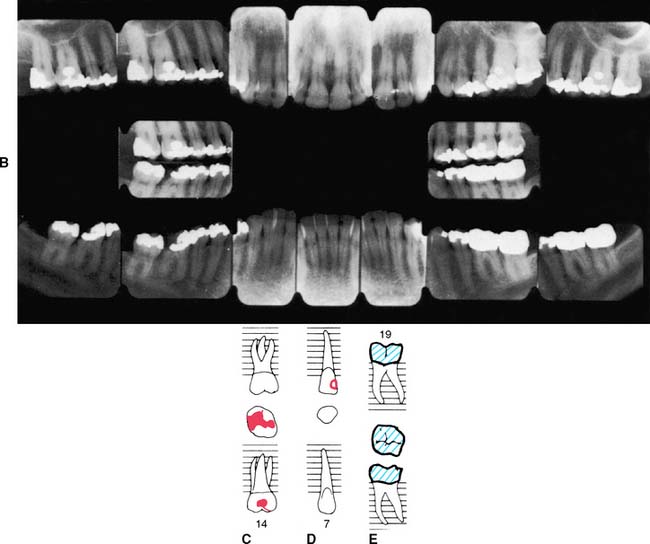

Radiographs provide essential information to supplement the clinical examination. Detailed knowledge of the extent of bone support and the root structure of each standing tooth is essential for establishing a comprehensive fixed prosthodontic treatment plan. Although radiation exposure guidelines recommend limiting the number of radiographs to only those that will result in potential changes in treatment decisions, a full periapical series (Fig. 1-23) is normally required for new patients so that a comprehensive fixed prosthodontic treatment plan can be developed. Patient exposure can be minimized by using a technique that provides the most information with a minimal need for repeat films and by using appropriate protection. The use of digital radiography can further help reduce radiation exposure.

Fig. 1-23 A to C, A full-mouth radiographic survey should enable the dentist to make a detailed assessment of the structure of each tooth and its bone support.

Panoramic films (Fig. 1-24) provide useful information about the presence or absence of teeth. They are especially helpful in assessing third molars and impactions, evaluating the bone before implant placement (see Chapter 13), and screening edentulous arches for buried root tips. However, they do not provide a sufficiently detailed view for assessing bone support, root structure, caries, or periapical disease.

Fig. 1-24 A panoramic film cannot be substituted for a full-mouth series because the image is distorted. Nevertheless, it is very useful for assessing unerupted teeth, screening edentulous areas for buried root tips, and evaluating the bone before implant placement.